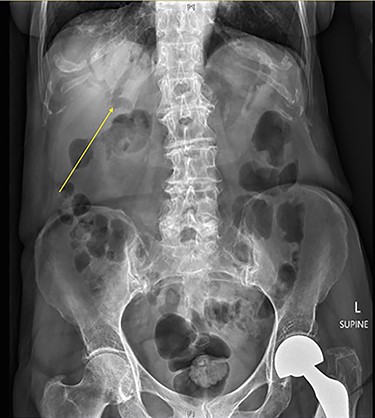

A 90-year-old female presented to the Emergency Department with right upper quadrant pain associated with nausea and persistent vomiting. She had been admitted seven months prior with acute necrotic cholecystitis, but given her advanced age, frailty, medical comorbidities and wishes to avoid surgery, she was managed with intravenous antibiotics and percutaneous cholecystostomy, which was removed eight weeks later. The patient was haemodynamically stable on presentation, but on examination had percussion tenderness in the right upper quadrant. Both abdominal X-ray and ultrasound demonstrated pneumobilia (Figs 1 and 2). A computed tomography (CT) of the abdomen showed a cholecystoduodenal fistula with a 60 × 30-mm gallstone in the third part of the duodenum causing gastric outlet obstruction (GOO), consistent with Bouveret syndrome (Fig. 3).